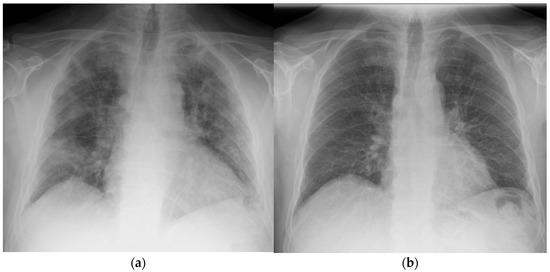

Figure 2. Chest X-ray taken of patient 1 at (a) day 1 prior to radiotherapy and (b) day 42 post treatment.

After the single dose of LDRT, improvement was observed clinically, biochemically, and radiologically. Prior to LDRT, the patient required 40% oxygen to maintain oxygen saturations of 95%. Forty-eight hours following LDRT, the patient was able to maintain oxygen saturations of 95% on room air. His PaO2/FiO2 (P/F) ratio (which can be used to categorise the severity of ARDS [10]) improved from 200 mmHg/F to 381 mmHg/F forty-eight hours post radiotherapy [Figure 1]. Biochemically, inflammatory markers improved with CRP reducing from 10.4 mg/dL at baseline to 1.4 mg/dL five days after LDRT. Notably, serum BNP dropped from 473 ng/L to 80 ng/L, which may imply a reduction in hypoxia-induced heart strain [Table 1]. Lymphocyte nadir was 0.63 (normal range being 1–4 × 109/L); values below 0.5 are considered to be significantly low [11]. Radiologically, by day 50, the previously seen bilateral interstitial infiltrates were no longer present; however, there did appear to be some persistent residual changes with coarsening of bronchovascular markings but no fibrosis [Figure 2].